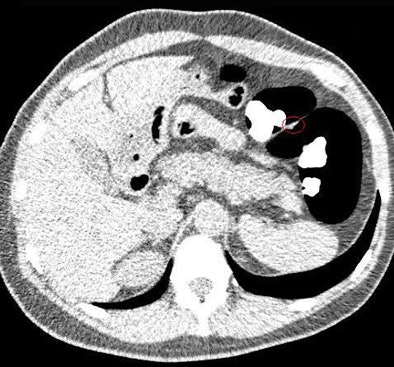

The biggest challenge was the residual fluid seen in some PEG-prepped cases owing to a lack of electronic cleansing software, especially when untagged feces were present, Yoshida said. For this reason, all studies were read using a primary 2D approach, with 3D confirmation of findings performed "whenever possible," he said.

Polyp locations were assigned to one of six colonic segments: rectum, sigmoid colon, descending colon, transverse colon, ascending colon, and cecum. Locations other than the cecum were further noted as proximal, mid, or distal within each segment. Polyp size was measured on 2D images using an electronic ruler, and the final diagnosis was made by consensus of the readers.

In the same-day preparation group, per-polyp sensitivities of the gastroenterologist and the radiologist were 91% and 73%, respectively, for polyps 6-9 mm. Per-polyp sensitivities in the reduced bowel preparation group were 86% and 86%, respectively, for polyps 6-9 mm. In both preparation regimens, sensitivities of the two readers were 100% for polyps 10 mm or larger, Nagata and his colleagues reported.